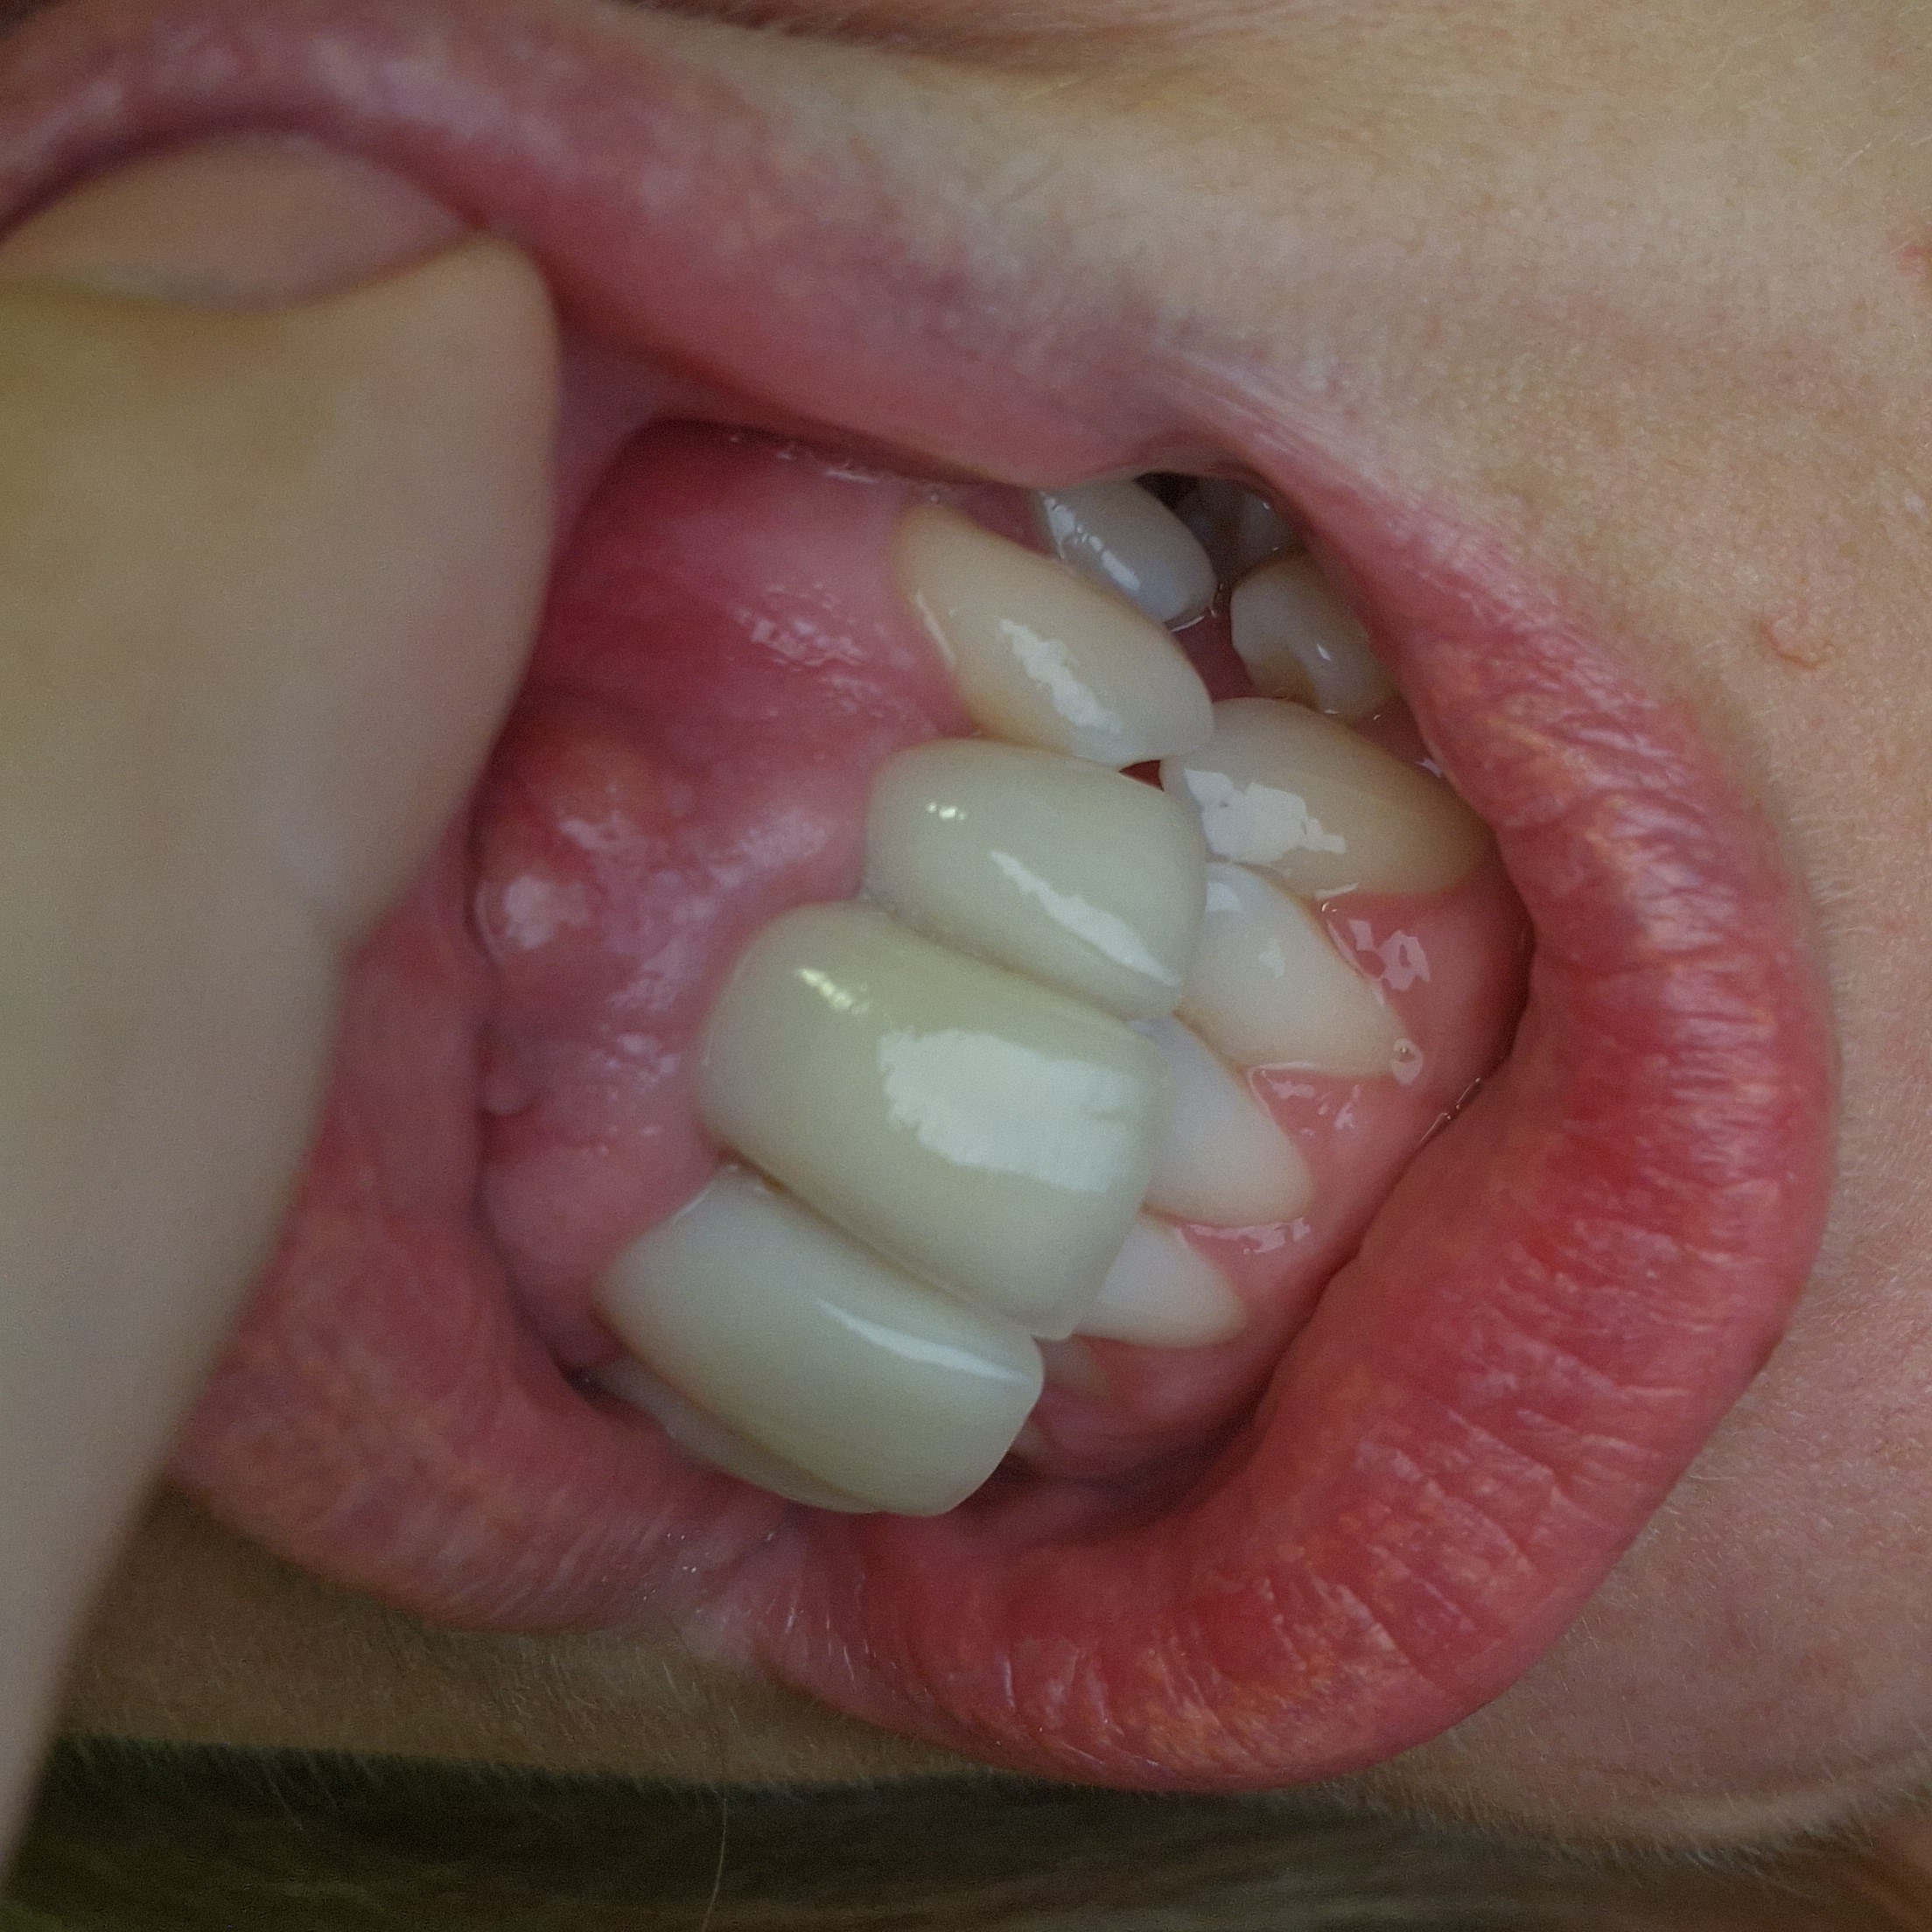

Ik val maar meteen met de deur in huis.. Ik ben dood ongelukkig door de definitieve kronen die afgelopen donderdag zijn geplaatst. (Zie foto's van voor eigen tanden en na met kronen) Wegens medische redenen moest ik overgaan op 4 kronen (de vier voorste tanden). Aangezien ik verder tevreden was over mijn eigen tanden, echter dat sommige iets terug/scheef stonden, heb ik aangegeven dat ik graag de zelfde vorm van mijn eigen tanden wil aanhouden. Echter is dit niet gebeurd. De kronen staan erg naar voren en zijn enorm lang. Ook mijn tandvlees is veel hoger dan het normaal was. Tijdens het plaatsen van de definitieve kronen heeft de tandarts niks besproken en niks vooraf laten zien. Ik dacht dat hij ze zou plaatsen om het vervolgens met mij te bespreken. Maar hij had ze al meteen definitief geplaatst. Ik schrok me kapot toen de spiegel voor me kwam (door de assistente). De tandarts verdween na de plaatsing meteen uit de ruimte. Ik wist niet hoe snel ik weg wou daar. De dag erna besloot ik de tandarts te contacteren om het te bespreken en eventueel iets aan te passen, aangezien ik er niet van heb kunnen slapen. Helaas is de praktijk nu gesloten tot de 26ste ivm vakantie. 2 dagen erna kreeg ik hevige pijn, Hiervoor naar de noodtandarts moeten gaan (op zondag). Maandag nog een keer naar een andere diensttandarts moeten gaan aangezien een deel van mijn gezicht begon op te zwellen en de pijn nier uit te houden was. Wellicht betreft het een ontsteking waardoor ik een wortelkanaalbehandeling moet ondergaan zodra mijn eigen tandarts weer zit. Ondertussen antibiotica gekregen. Sinds vandaag neemt de pijn/zwelling iets af. Ik ben enorm verdrietig door dit allemaal. Ik hoop dat jullie mij wat raad kunnen geven, hoe ik dit nu het beste kan aanpakken.

Ik heb foto's bijgevoegd hoe de stand eerst was en de stand nu met kronen. Op de foto duidelijk te zien dat de kronen meer een overbeet veroorzaken. Mijn lip hangt nu voor iets naar onder ivm verdikking van lip/wang door zwelling.

Ook als ik mijn normale lach aanhou voel ik de tanden in mijn onderlip steken. Gezien de extreme overbeet zijn woorden met de letter F een drama om uit te spreken. Ook mijn tandvlees is minder zichtbaar. Vooral het boogje tussen mijn voortanden. Komt dit nog goed?

Betreft de kronen: gaf de dienstdoende tandarts aan dat ze inderdaad enorm lang zijn en constateerde dat ik mijn mond in rust stand wegens de lengte van de kronen niet kan sluiten. Ook vond hij ze erg hoog geplaatst en de overbeet extreem. Hij gaf het zelfde advies als jou (Richard) het te bespreken met mijn huidige tandarts en te komen tot een goede oplossing. Zoieze de kronen korter maken. Maar gezien de stand etc zou het beter zijn om nieuwe te laten maken wat beter past. Maar dan gaat er weer een laag eigen tand verloren.

Morgen terug voor aanpassingen. Hij beloofde de noodkronen te maken en aan te passen totdat ik tevreden was én pas dan de definitieve precies zo na te laten maken. Ook extra voor gehapt. Echter zijn de noodkronen precies weer zo lelijk geworden als de eerste definitieve kronen. Gelukkig wel een stukje korter maar weer zo hoog geplaatst, de tandvleesbogen lelijk, en weer veel te bol..

( zie foto's met poging 2)

De incisale (snijlijn) komt nu beter overeen met uw oorspronkelijke stand. U trekt uw lippen nu in een gedwongen onnatuurlijke stand waardoor alles er ook anders uit ziet. De Cervicale grens( bovenkant tegen tandvlees) is iets anders dan oorspronkelijk maar dat kan gebeuren afhankelijk v hoeveel men heeft weg geslepen. u trekt uw lip ook hoger op, hoger dan dat het in een normale stand zou zijn. Als uw lip normaal zou hangen denk ik dat u niet zult zien dat de cervicale lijn zo hoog zou zijn. Ik zou een half jaar wachten met definitief cementeren v d kronen, en pas als u helemaal tevreden en klachtenvrij bent def cementeren. Ik schrik dat een tand getrokken is bij het verwijderen v d kronen. Vraag mij dan ook af of uw parodontium ( ophanging tandvlees) wel gezond genoeg is om kronen te rechtvaardigen. Zou dan ook de x-foto v voor aanvang behandeling willen zien. U kunt een kopie digitaal vragen. Bij het afmaken v d wkb worden nieuwe x-foto gemaakt, vraag die dan ook gelijk en de x-foto v d dienst. Ben benieuwd wat er op te zien is.

Over deze kronen ben ik nog steeds niet te vreden: kleur wijkt enorm af, vooral in een bepaald daglicht. Ook de boog vind ik nog steeds niet mooi, tandvlees (papil) komt niet mooi uit, erg onsymmetrisch..

Daarbij kronen ook erg bol, boven bij het tandvlees steekt de kroon ver uit tov het tandvlees.